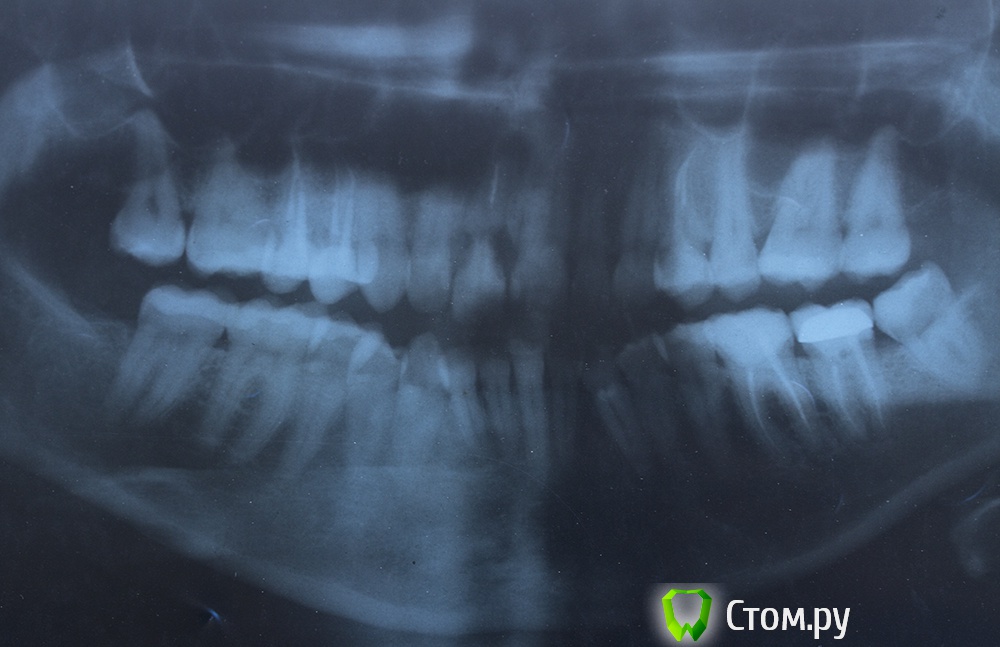

AnaY007 Опубликовано 27 октября, 2014 Автор Поделиться Опубликовано 27 октября, 2014 (изменено) +1, нужны снимки. Но к сожалению оценить качество съемного протеза в полном объеме можно только на очном осмотре. Выкладывайте rg и фото протеза и во рту и внеRG, потом снимок протез стоит в ряду, но отстает от десны, и последний десна прилегает, зато рот не смыкается никакпо цвету там пломбы на верхних резцах окрасились от крови, надо будет переставлять, на нижних и протезе "родной" цвет, просто фото протеза Изменено 27 октября, 2014 пользователем AnaY007 Ссылка на комментарий